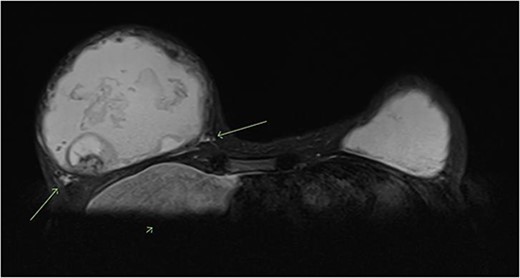

A magnetic resonance imaging (MRI) scan of the breasts showed a retroglandular breast implant/injectable filler measuring 1015 cc in the right breast. There were irregular margins and some signal external to the fibrous capsule, suggestive of an intracapsular and extracapsular implant rupture. Within the right breast filler, there was heterogeneous signal and a focal ovoid heterogeneous component with internal vascularity measuring 4.3 × 3.4 cm, at 8 o’clock 10 cm from the nipple. This was reported to be either fat necrosis or a breast implant-related neoplasm. There were no suspicious lesions in the right breast parenchyma and no axillary lymphadenopathy. The left breast also showed a retroglandular breast implant/injectable filler measuring 583 cc, and no suspicious lesions within the filler or the breast parenchyma (Fig. 1).

T2 weighted MRI of bilateral breasts—showing irregular borders of the fibrous capsule, heterogeneous material within the capsule, an intracapsular lesion, and extracapsular signal, suggestive of intracapsular and extracapsular breast implant rupture.